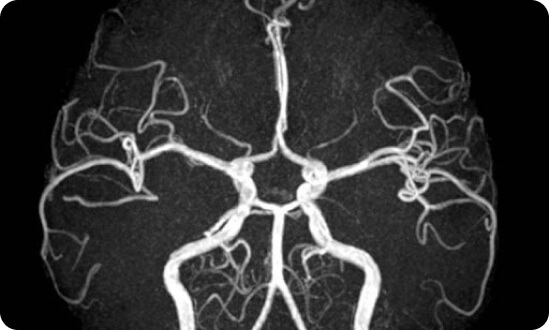

MRI Chụp mạch máu

- Cuộn thu mạch máu ngoại biên và toàn bộ chi dưới 36 kênh

- Độ chính xác cao

- Chụp mạch máu não trong và ngoài sọ, mạch tạng, mạch ngoại biên nhanh, rõ nét chẩn đoán chính xác hẹp, tác, dị dạng mạch não không sử dụng đối quang từ